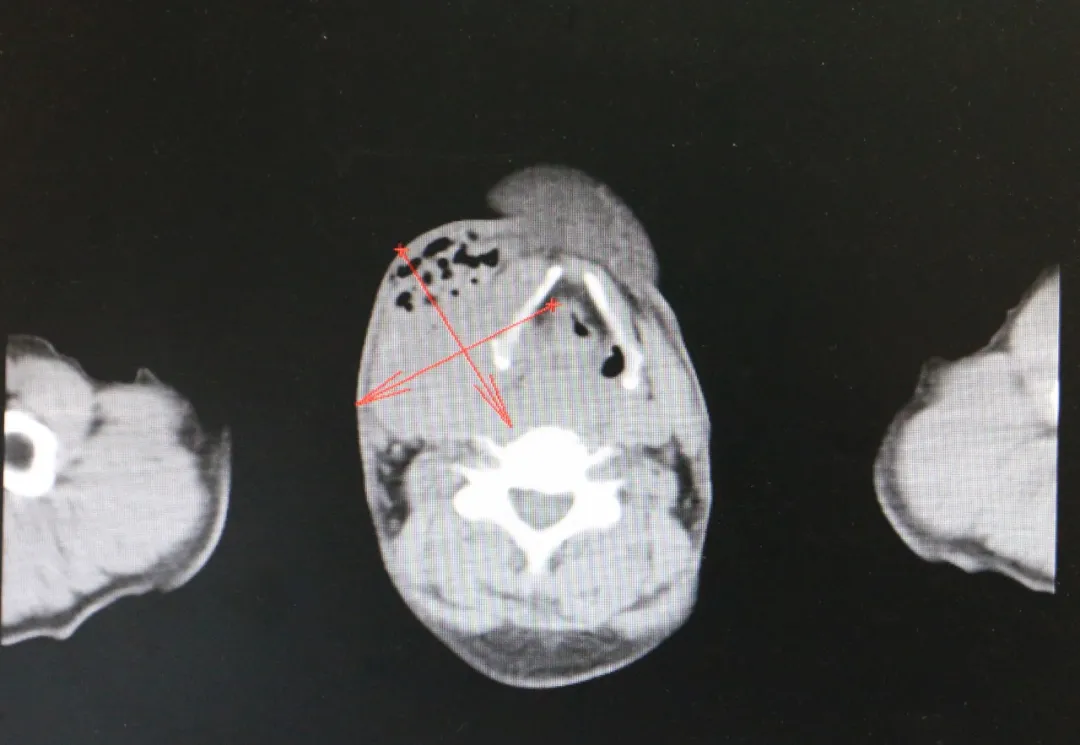

近日,济南南郊医院肿瘤科葛新华主任带领治疗团队,成功为一位50岁的下咽癌患者实施了微创介入治疗,术后患者恢复情况良好。

这位患者曾辗转北京与青岛的多家三甲医院,但治疗效果并不理想。在绝望之际,他了解到济南南郊医院肿瘤科葛新华主任的治疗团队,于是抱着最后的希望来到该院就医。经过葛新华主任团队的细致检查与评估,为患者量身定制了微创介入治疗的手术方案。

DSA微创介入灌注栓塞术,是一种在不开刀暴露病灶的情况下,通过微小通道或人体原有管道,在DSA影像设备的引导下,对病灶进行精准定位与治疗的先进技术。该技术通过微创穿刺股动脉进入血管系统,精准插入肿瘤病灶,注射血管栓塞剂对肿瘤病灶周围血管进行栓塞,从而切断肿瘤细胞的营养供应通道,使其无法增长与转移。同时,通过导管注入高浓度的化疗药物,对肿瘤组织进行破坏,直至将其“饿死”消亡。整个治疗过程安全、高效,患者术后可安返病房,正常生活饮食不会受到任何影响。